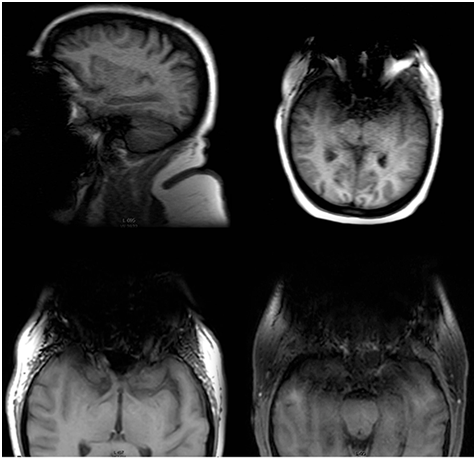

Одним из важных параметров МРТ-изображений является Echo train length (ETL), который, по сути, определяет количество строк К-пространства, заполняемых за одно время повторения TR.

Для ИП типа простого SE (спин-эхо) ETL равен 1, т.к. заполняется одна строка. Для быстрого спин-эха (FSE – Fast SE) с такими же TR и TE этот параметр больше 1 – заполняется по несколько строк сразу. Для UltraFSE и других сверхбыстрых последовательностей – все строки за один TR. Чем выше ETL, тем меньше в итоге времени требуется на получение изображения, но при этом контраст снижается, а шум возрастает. Разумное значение ETL выбирается оператором с учетом задачи и исследуемого органа. Например, для подвижных органов (сердце, легкие, кишечник и т.п.) использование ИП с высоким ETL позволяет снизить влияние движений на резкость слайсов.

Из-за явного влияния на контраст и шум изображений этот параметр полезен как при выборе оптимальных серий, так и при анализе ошибок и устранении выбросов из датасета.